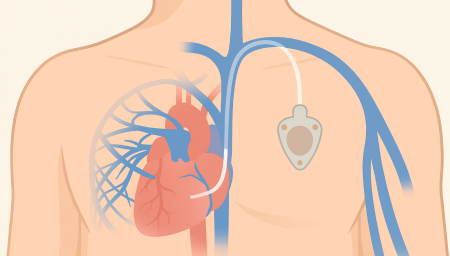

항암관(Chemoport)삽입

Chemoport는 항암제처럼 자극이 강한 약물을 안전하고 안정적으로 투여하기 위해 흉부 피부 아래에 이식하는 중심정맥 사용 포트입니다. 팔 혈관이 약하거나 반복 주사로 인한 통증이 걱정되는 환자에게 도움을 줄 수 있으며, 장기간 치료가 필요한 경우 편안하게 항암 치료를 지속할 수 있도록 설계되어 있습니다.

항암관(Chemoport)삽입 과정

국소마취 후 작은 절개를 시행 (보통 쇄골 아래 약 2~3cm 정도 절개)

정맥에 카테터 삽입 후 포트와 연결

방사선으로 카테터 위치 확인

피부 봉합 후 소독 드레싱